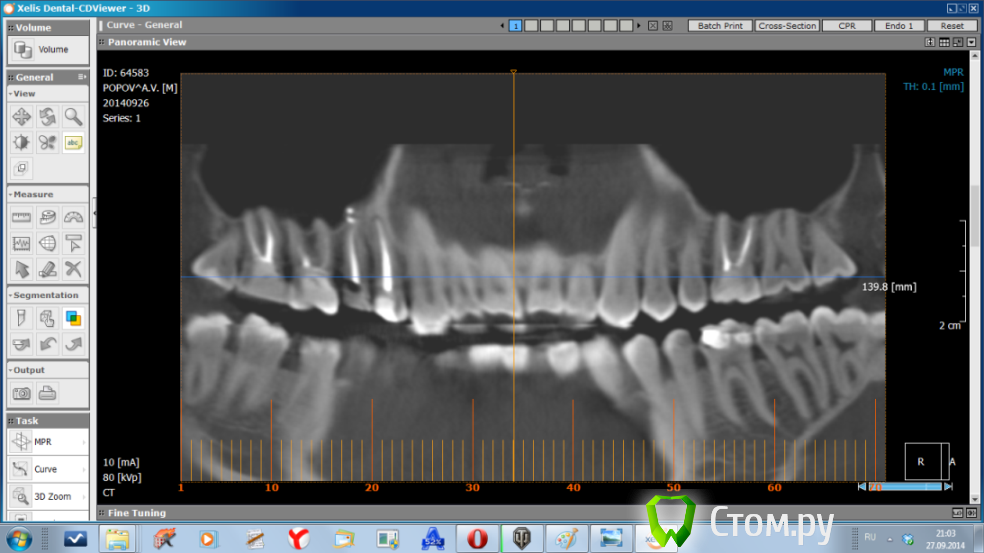

SDC Опубликовано 1 октября, 2014 Поделиться Опубликовано 1 октября, 2014 (изменено) Дайте, пожалуйста, срезы КТ в трансверсальной (горизонтальной) проекции. А еще лучше - выложите zip-папку Data (c .dcm файлами) на облако и дайте ссылку на скачивание.Скачал, открыл. Вижу одну единственную маленькую причину, которая сначала привела к остаточному пульпиту, а сейчас к хр. периодонтиту. (если, конечно, мы рассматриваем 15 зуб, как единственный причинный) Это доп.канал, расположенный палатинально. очень часто анатомия верхний 5-х зубов именно такова: один магистральный канал, который в апикальной части расходится на 2, "ласточкин хвост". Срез в апикальной части корня, где контурируется 2 слившихся корня, намекает на подобную анатомию.Это предположение получит подтверждение при:1. Наличии чувствительности на холодное и/или горячее в первые дни после эндолечения 15 зуба. (из анамнеза)2. Положительной динамике после повторной обработки канала.3. При визуализации бокового (палатинального) ответвления магистрального канала в микроскоп. http://s017.radikal.ru/i432/1410/b0/89dec2d707be.jpghttp://s019.radikal.ru/i624/1410/12/8beb2b221607.jpghttp://s009.radikal.ru/i308/1410/a2/22f792e49f66.jpg Изменено 1 октября, 2014 пользователем SDC 1 1 Ссылка на комментарий

dr-krasnov Опубликовано 1 октября, 2014 Поделиться Опубликовано 1 октября, 2014 Коллега, а пломбировочный материал в пазухе вас не смущает? Ссылка на комментарий

SDC Опубликовано 1 октября, 2014 Поделиться Опубликовано 1 октября, 2014 Коллега, а пломбировочный материал в пазухе вас не смущает?Нет, так же, как это не смущает слизистую пазухи 1 Ссылка на комментарий

SDC Опубликовано 1 октября, 2014 Поделиться Опубликовано 1 октября, 2014 Будем надеяться, что Вы правы и доставать его потом из воспаленной пазухи не придется.Эндоскопически грамотному ЛОРу это не предоставит труда ни сейчас, ни позже, если для этого появятся показания.Остаточный пульпит, на мой взгляд - основная причина жалоб на сегодняшний день. 1 Ссылка на комментарий